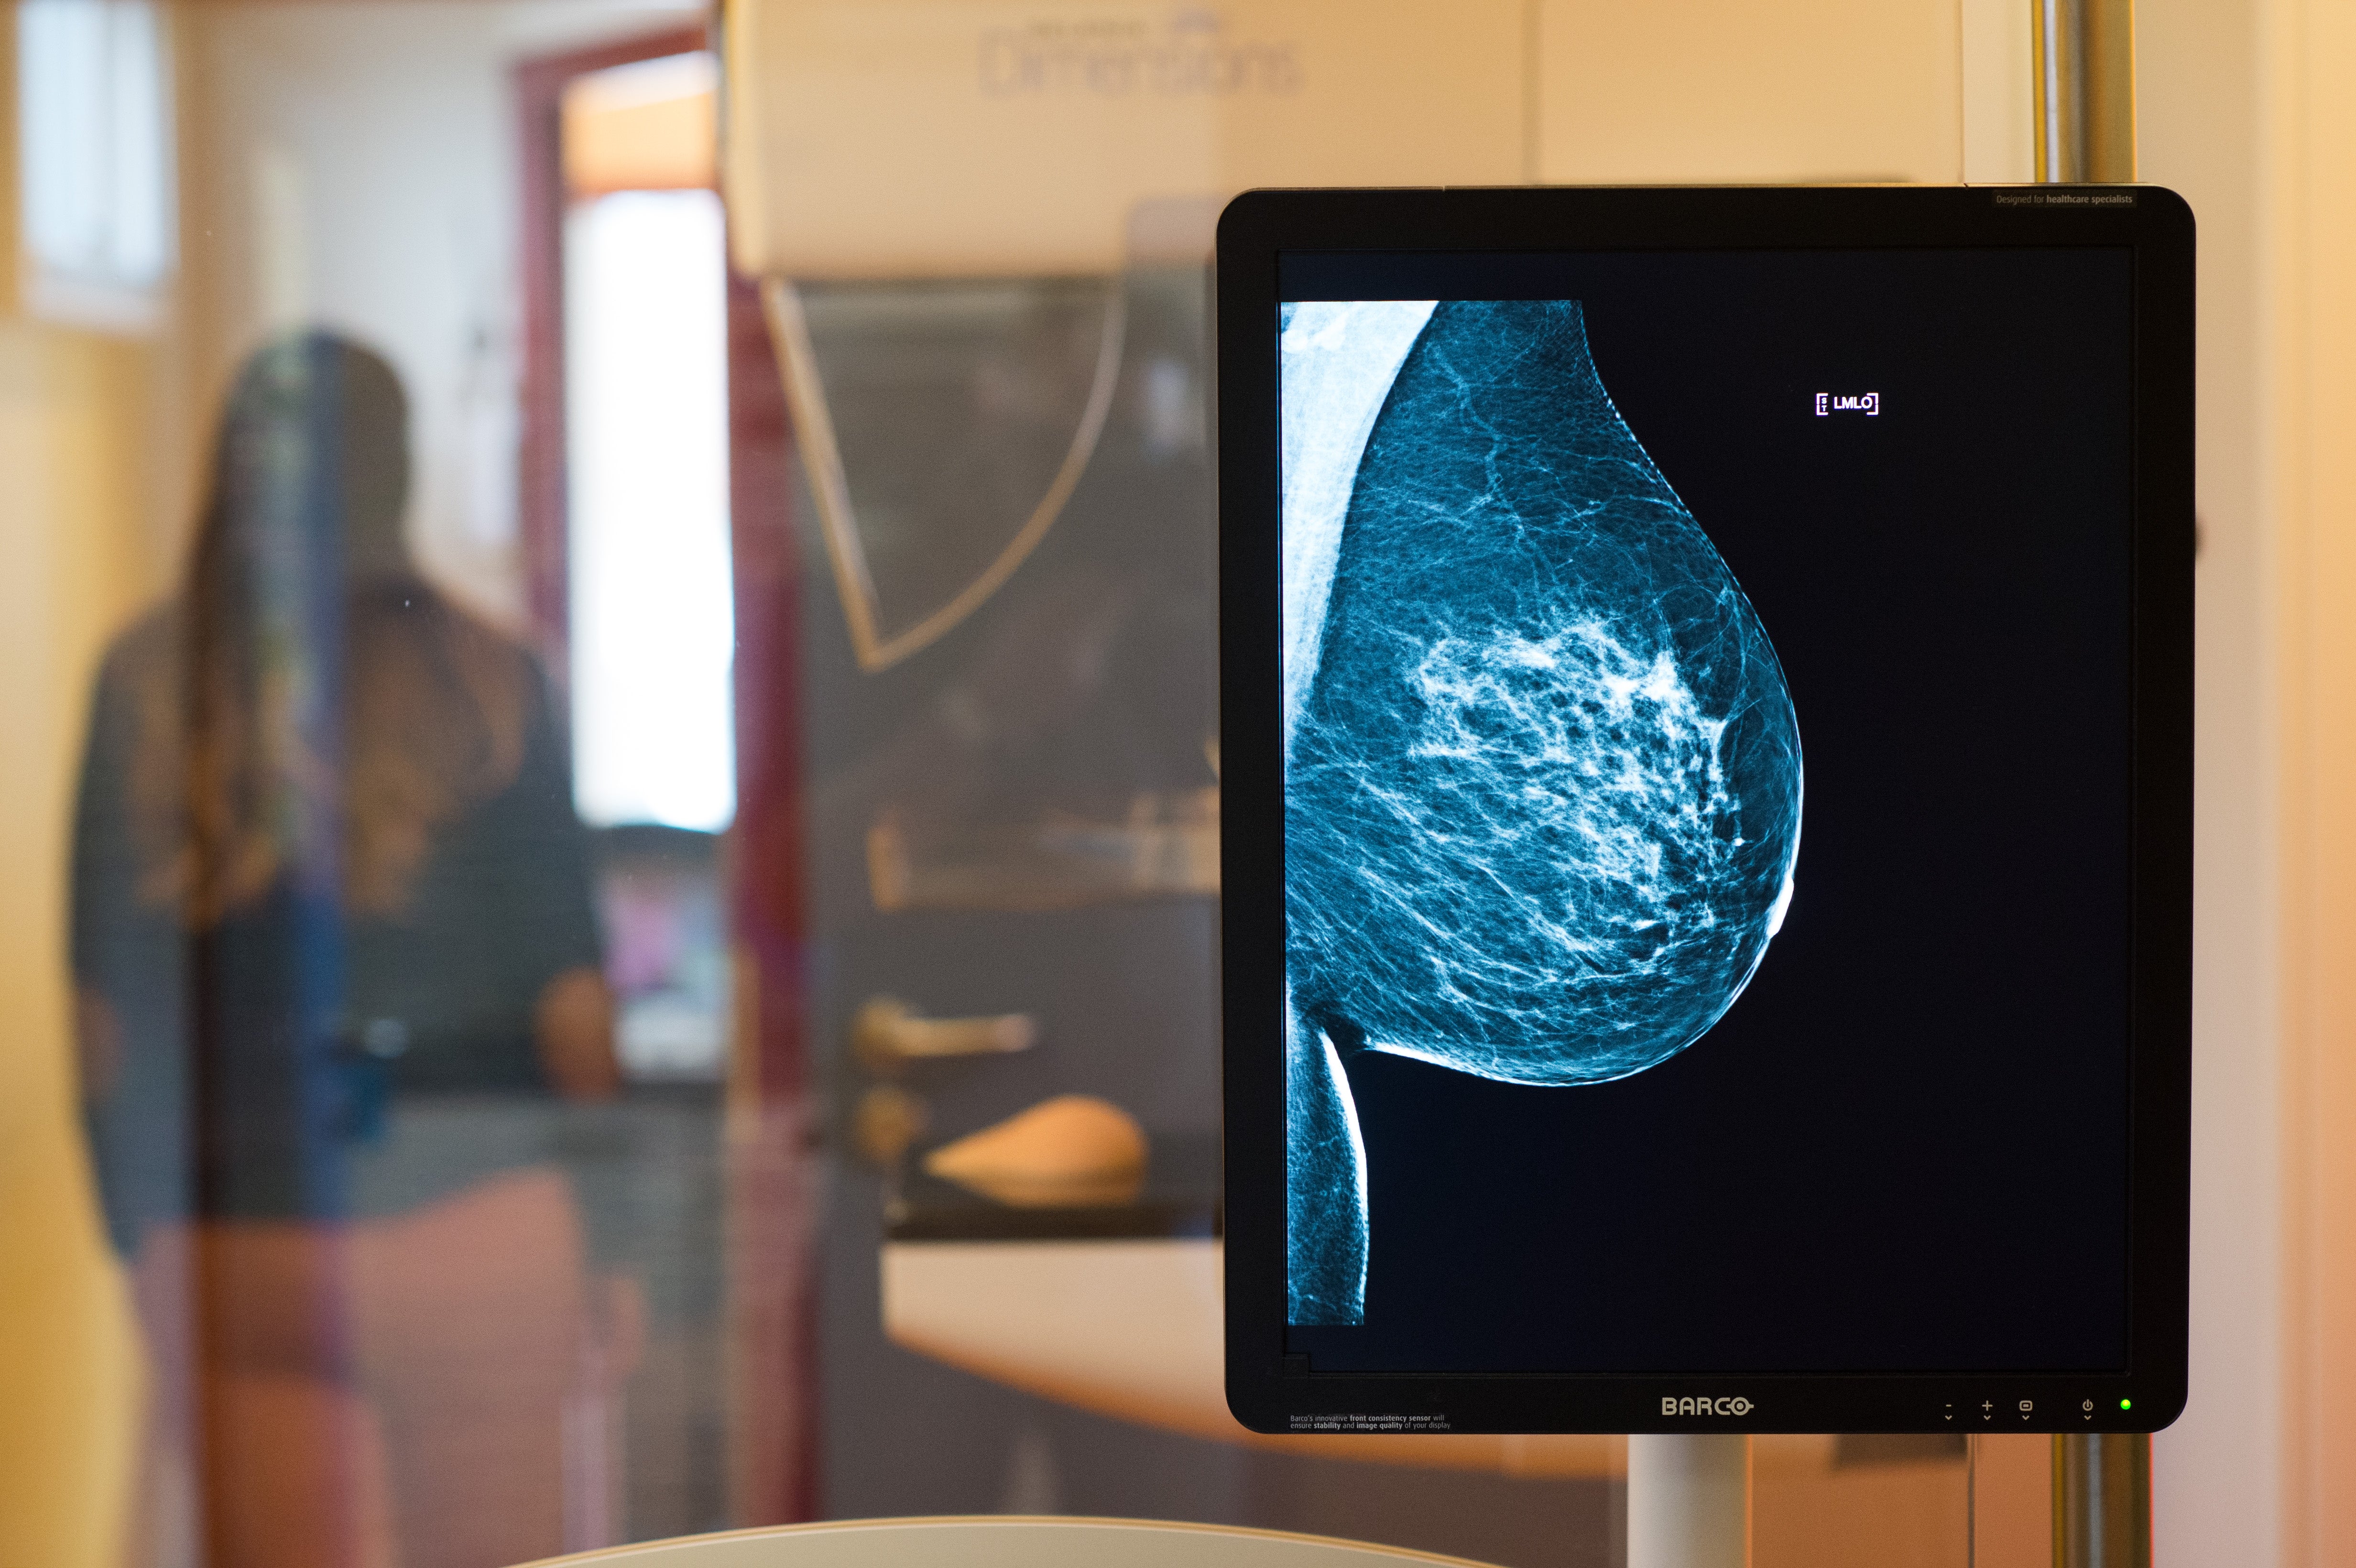

Auffälligkeiten bei mammographie screening. Auffälligkeit bei Mammografie. Beurteilt hingegen eine der Ärztinnen oder einer der Ärzte die Mammographie als auffällig wird zusätzlich eine Fachärztin oder ein Facharzt hinzugezogen. Die Mammographie ist eine Röntgenuntersuchung der weiblichen Brust.

Sehr dichtes Drüsengewebe erschwert die Beurteilung der Mammographie-Aufnahme und das Risiko Tumore zu übersehen nimmt zu. Das Mammographie-Screening steht immer wieder wegen vermeintlich vieler Falschdiagnosen in der Kritik sagte Vanessa Kääb-Sanyal Leiterin der Geschäftsstelle der. Sie eignet sich zur Brustkrebsfrüherkennung weil sie schon sehr kleine nicht tastbare Tumoren in einem frühen Stadium sichtbar machen kann.

Ärztliches Gespräch Die Ärztin der Arzt bespricht den Befund sowie die empfohlenen weiteren Diagnoseschritte. 22032018 Bei einem falsch-positiven Befund handelt es sich im Mammographie-Screening um eine Auffälligkeit im Röntgen-Bild die allein anhand der Screening-Mammographie noch nicht als eindeutig gutartig eingestuft werden kann. Was passiert bei einer auffälligen Mammographie.

In diesen Fällen wird die Frau zu einer ergänzenden Untersuchung wie Ultraschall eingeladen. In einigen Screening-Zentren kann die Diagnose bei einem einmaligen Besuch geklärt werden. Die Mammographieaufnahmen werden innerhalb von sie-ben Tagen von zwei Radiologen bezüglich möglicher Auffäl-ligkeiten unabhängig voneinander untersucht.

Diese führen untersuchende Radiologinnen bei Ihnen ergänzend zur Tastuntersuchung insbesondere dann durch wenn beim Abtasten Ihrer Brust Auffälligkeiten festgestellt wurden. An Brustkrebs sterben 17000 Frauen allein in Deutschland jedes Jahr. Stellen beide Typisches mammographisches Bild eines invasiven Mammakarzinoms Brustkrebs mit Nachweis eines sternförmig begrenzten Verdichtungsher-des.

Antwort von Trini am 01122019 2303 Uhr. Bei etwa 2 von 1000 im Mammographie-Screening untersuchten Frauen bei denen die Mammographie unauffällig war wird vor der nächsten Einladung Brustkrebs festgestellt.